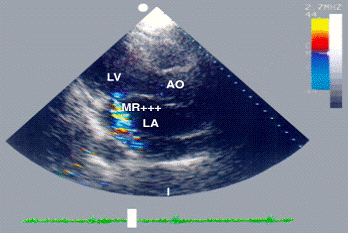

Рис. 17. Двухмерная цветная допплер-эхокардиограмма при митральной недостаточности (LV - левый желудочек сердца, LA - левое предсердие, АО - аорта): в систолу зафиксирован мозаичный турбулентный поток митральной регургитации 3 степени (MR+++) через не полностью сомкнутые створки митрального клапана